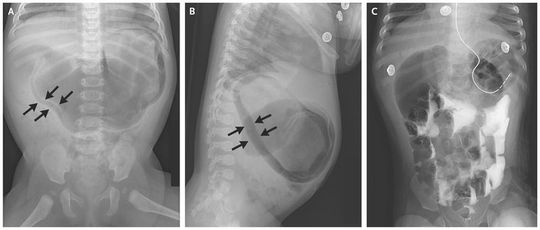

A 4-month-old girl presented with poor feeding and nonbilious emesis. At 1 month of age, she had been hospitalized briefly for emesis but was able to feed until 1 week before presentation. She appeared well, and her abdomen was soft but distended. Laboratory investigations revealed a hypochloremic metabolic alkalosis, and radiographs showed gastric pneumatosis (Panels A and B, arrows). A nasogastric tube was placed, and intravenous administration of fluids was started. Radiography of the upper gastrointestinal tract with contrast revealed contrast medium passing into the small intestine; follow-up images showed resolution of pneumatosis and a “double bubble,” which suggested duodenal obstruction (Panel C). Duodenal obstruction caused by a duodenal web was identified intraoperatively, and a duodenoduodenostomy was performed, which resulted in resolution of symptoms. Gastric pneumatosis is rare and probably results from mucosal disruption due to ischemia or infection that allows gas to infiltrate into the wall of the stomach. In newborns, gastric pneumatosis is associated with necrotizing enterocolitis, but increased intragastric pressure from severe obstruction caused by duodenal blockage, pyloric stenosis, or a lactobezoar may also produce gastric pneumatosis.